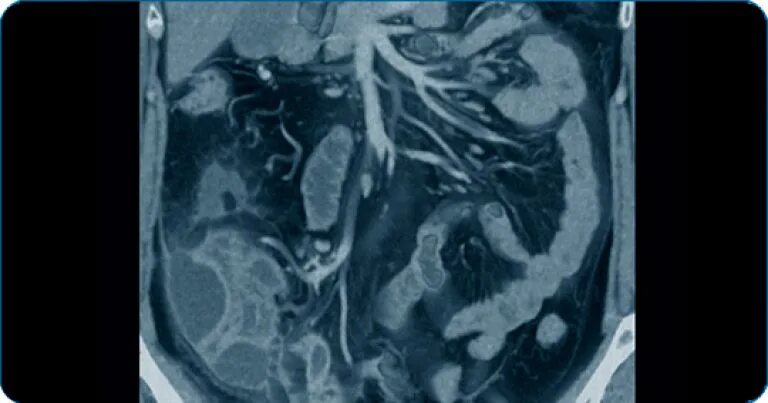

Что входит в мрт забрюшинного пространства